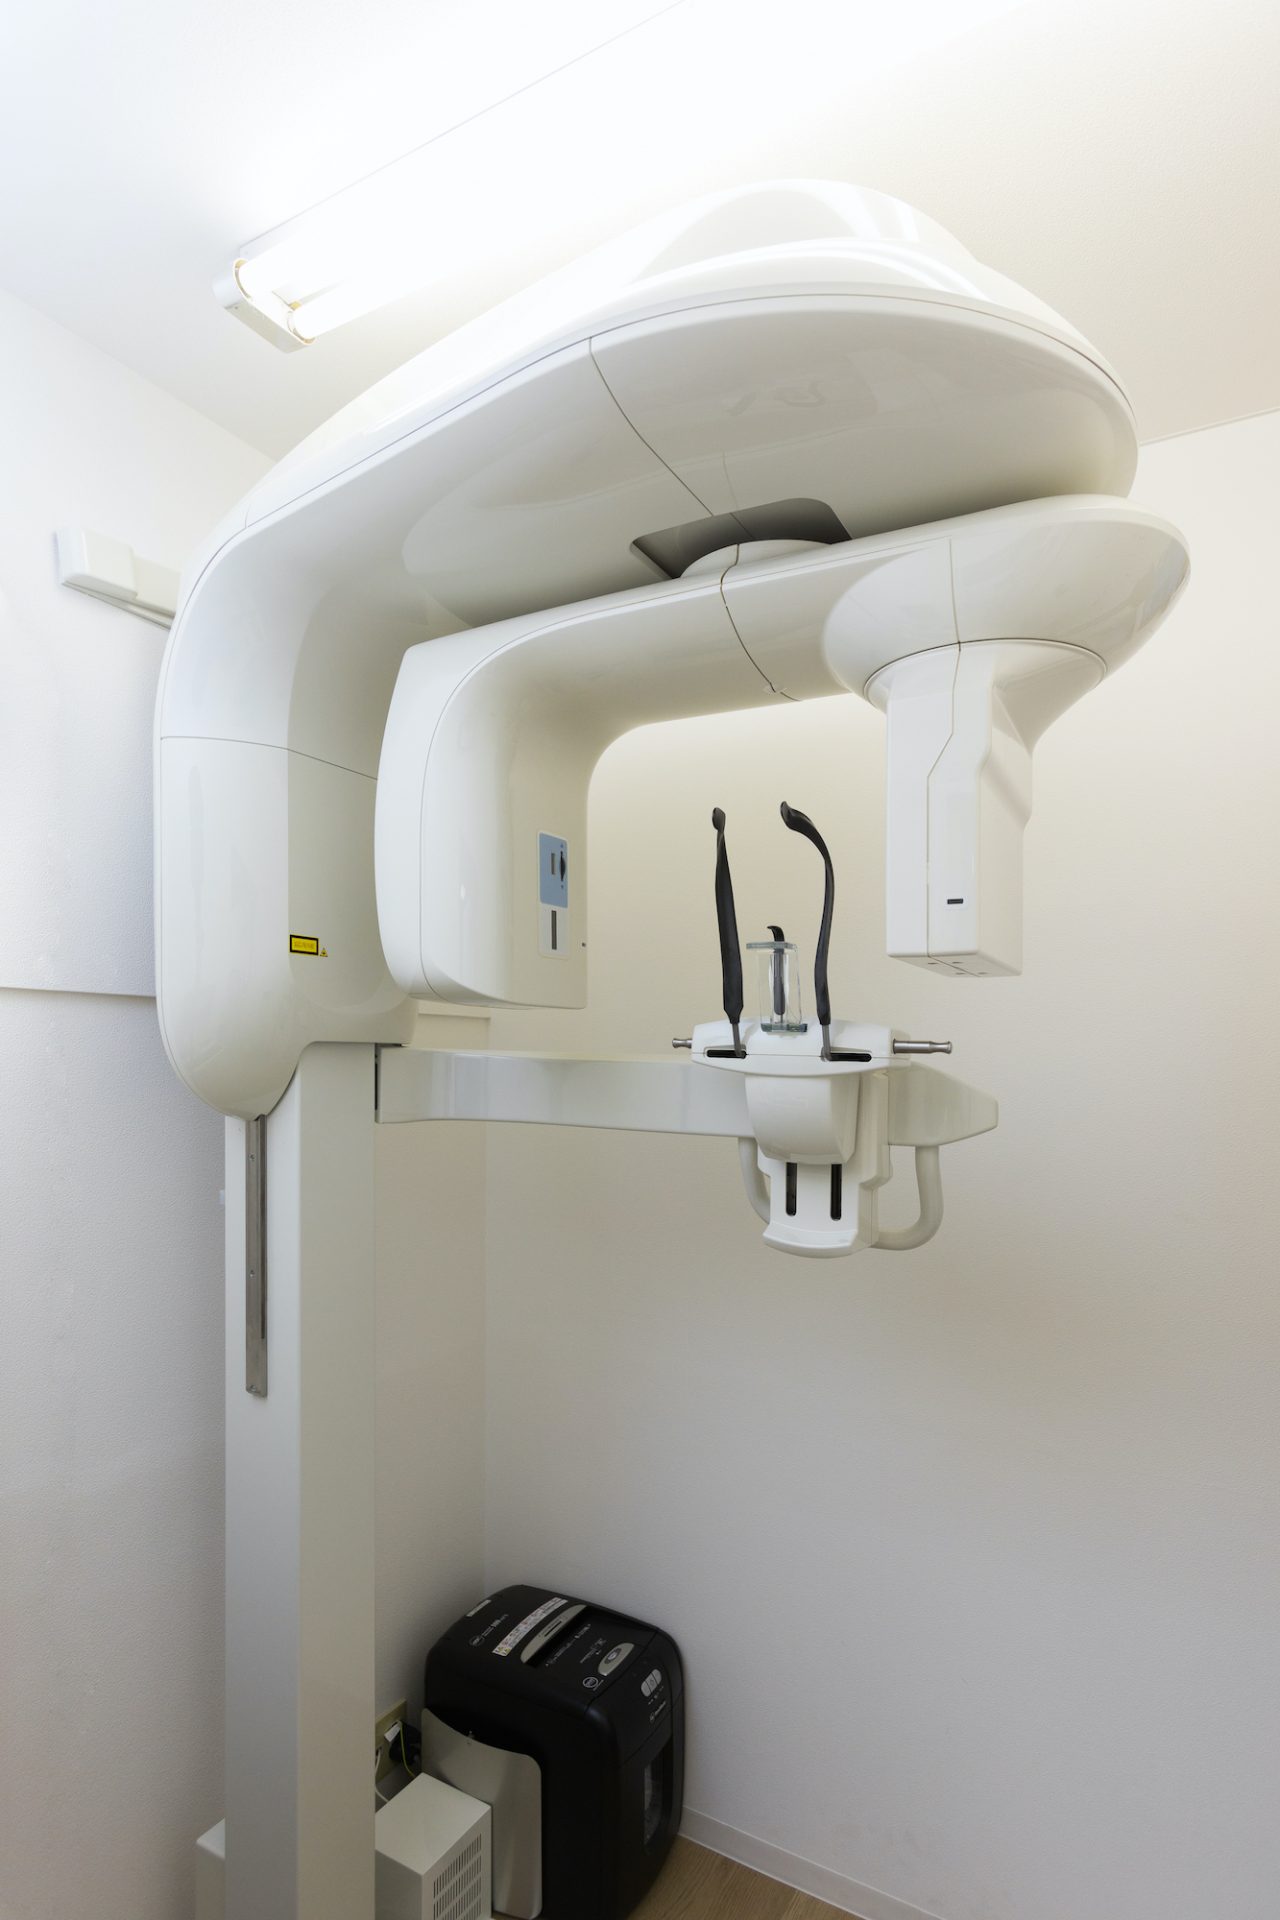

歯科用CTを導入しています

パノラマと3Dセンサーを駆使した回転式デジタルレントゲン。

デジタルにより従来のフィルムを使用したレントゲン撮影に比べ、人体に受ける放射線の量を約1/4~1/10に抑える事が可能に、またCT(3D)機能により断層写真、立体的な撮影ができますので、インプラントのみならず、あらゆる歯科診療でより正確な診断と安全確実な診断が行えるようになりました。

CT撮影も実行照射時間の短縮により、患者様に必要以上のX線照射をすることなく診査・診断ができ、体にも安全です。